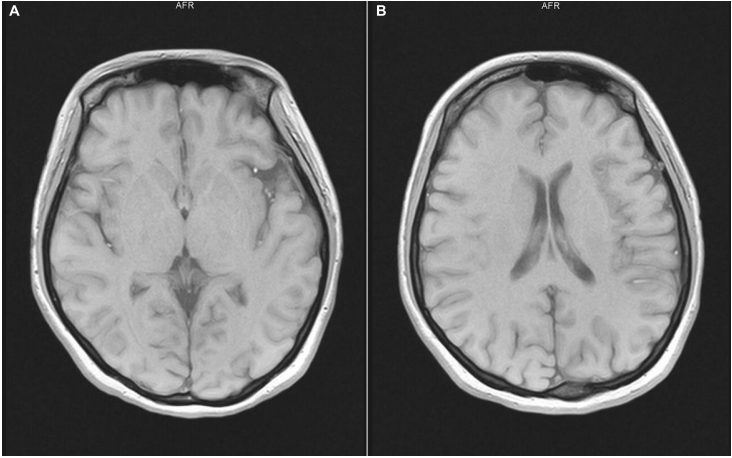

实验室检查显示,患者血细胞计数、凝血功能、肾功能、肝功能和甲状腺功能正常,心电图(ECG)和脑电图(EEG)正常。头颅磁共振扫描显示双侧额叶微缺血(图1)。

图1.头颅磁共振扫描显示双侧额叶微缺血